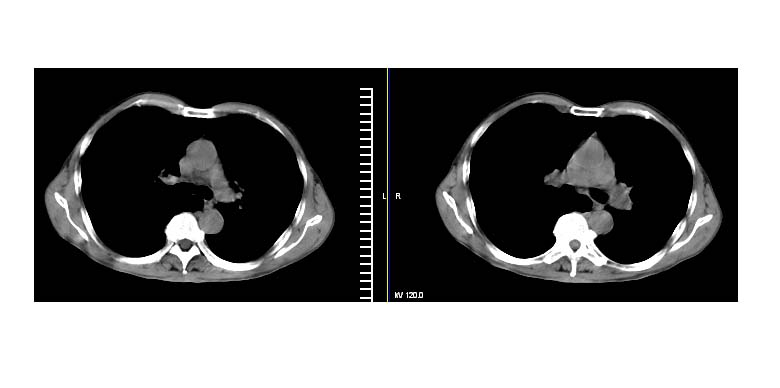

标题: CT11019:男性,66岁。发烧5-6天。治疗后无明显好转。 [打印本页]

标题: CT11019:男性,66岁。发烧5-6天。治疗后无明显好转。

左下肺中央型肺癌伴阻塞性肺炎\\肺不张可能性大,建议支纤镜检查.

1.左肺门似可见一小块影,由此考虑中央型肺ca并阻塞性肺炎改变;

2.左下叶背段肺tb(干酪性肺炎)?

3.单纯肺感染?建议进一步检查。

左下肺中心性肺癌伴下肺不张及周围阻塞性炎症

左下肺中央型肺癌伴阻塞性肺炎\\肺不张可能性大,建议支纤镜检查

左侧胸廓偏小,左下梭形高密度影,考虑阻塞性肺炎.

左肺门下分增大见有结节影,基底干及分支显示不清,下叶体积缩小,呈片带状机磨玻璃样影显示。支持考虑左下肺中心型肺癌伴阻塞性肺炎及部分肺不张。建议纤支镜检查